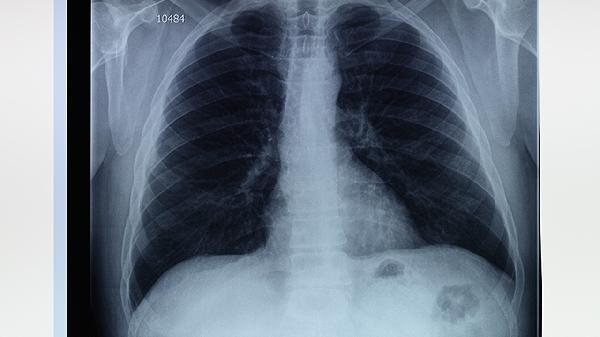

肺气肿肺大泡怎么治才能呼吸更顺畅

肺气肿和肺大泡的治疗方式包括戒烟、药物干预、吸氧、肺部康复锻炼以及手术等,这些方法有助于改善呼吸功能。肺气肿通常与长期吸烟或空气污染有关,而肺大泡则多由肺泡结构受损引起。